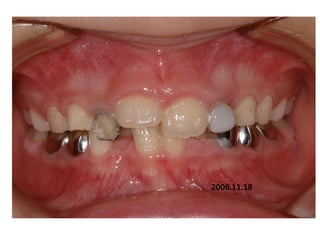

1999.04.05/F

C.C

• Diastema, flattened lower ant.

Dx

• Mentalis action, heavy labial frenum

Goal

• Establish normal lip tone

2006.02.08

2004.05.13

2006.12.27 10m

2007.05.08 1y 3m

2008.07.30 2y 5m

2009. 02.18.3y

2009.08.11 3y6m

2010.06.15 4y4m

2012 02 01

out of Tr 2yr